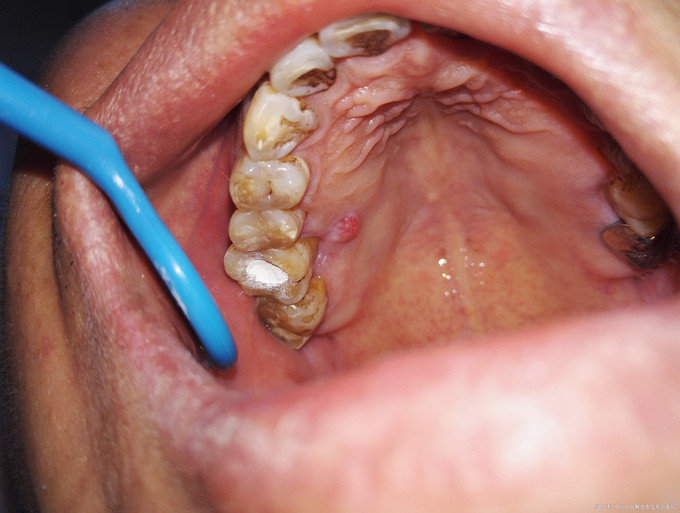

检查:16牙冠完整,牙龈红肿,腭侧可见一窦道,PD=13-5mm,叩痛(++),松动II度。 X线示:16髓腔部分钙化,根管影像不清晰,未见根充影像,根尖周大面积低密度影,近远中根周膜增宽。

诊断:16牙周牙髓联合病变(逆行性牙髓炎) 治疗计划:16RCT+牙周基础治疗+改良翻瓣术 初诊:常规局麻下开髓揭顶,髓腔钙化,少量髓石,超声探查根管,拔髓,根管较细,疏通,封EDTA,一周后复诊。 复诊1:去暂封,继续探查根管,P、MB通畅,DB根尖区钙化,电测根长:P=MB=17.5mm,DB=15mm,EDTA下手扩+机扩+protaper根备至F2,生理盐水+双氧水反复交替冲洗,干燥,CP棉球+ZOE暂封,约日复诊。 复诊216消毒,局麻下洁治,刮治,小翻瓣术,搔刮出大量肉芽组织及少量牙石,根面平整,浓替硝唑冲洗,复位,OHI,约日复诊。 复诊3:腭侧窦道基本愈合,去暂封,超声荡洗,干燥,试尖可,糊剂+热牙胶根充,棉球+ZOE暂封,2周后复诊树脂充填。 复诊4:复诊常规树脂充填,腭侧窦道愈合(忘记拍片子,太遗憾,但是患者1个月后会过来复查)。